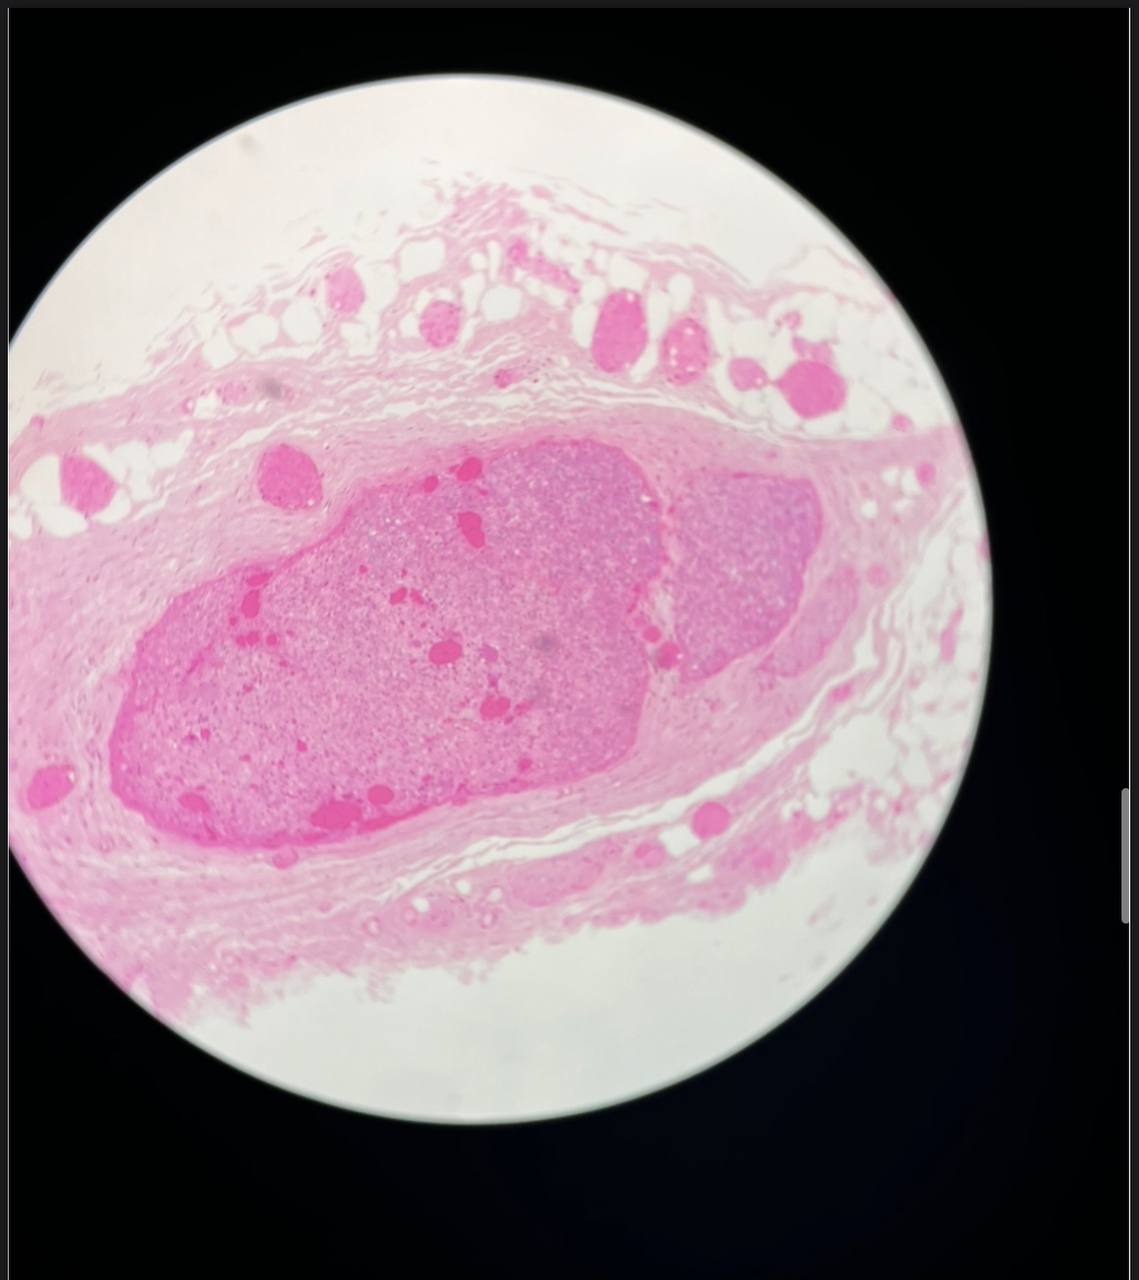

adipose C.T tissue

thin skin

land mark: فيها منحنيات كثير

thick skin

landmark: thick keratin layer

A horny layer

B clear cell layer

C granular layer

D prickle cell layer

E germinal layer

F dermal papillae

A thin epidermis

B hair follicle

C sebasceuos gland